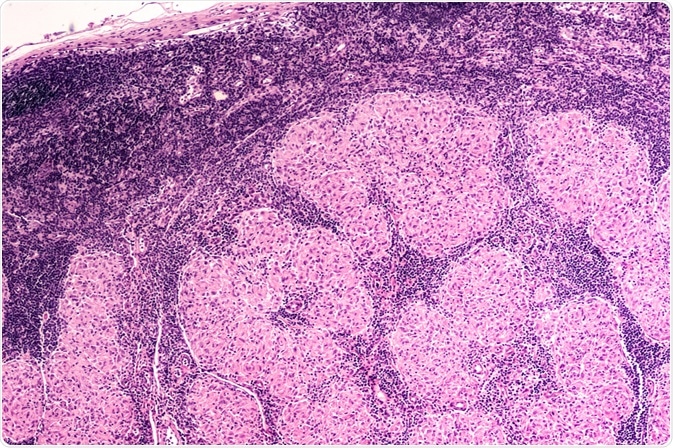

Micrograph of an enlarged lymph node showing non-caseating granulomas of sarcoidosis. Image Credit: David A Litman / Shutterstock